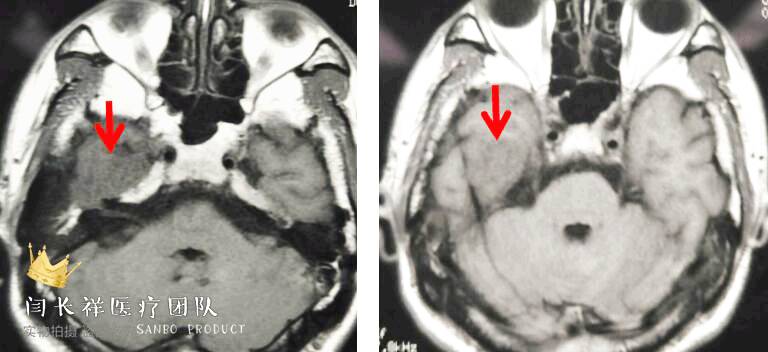

中颅窝-颞下窝占位

术前MRI轴位T1扫描示病灶呈等信号。

术前MRI轴位T2扫描示病灶侵及面神经膝段及中耳骨质。